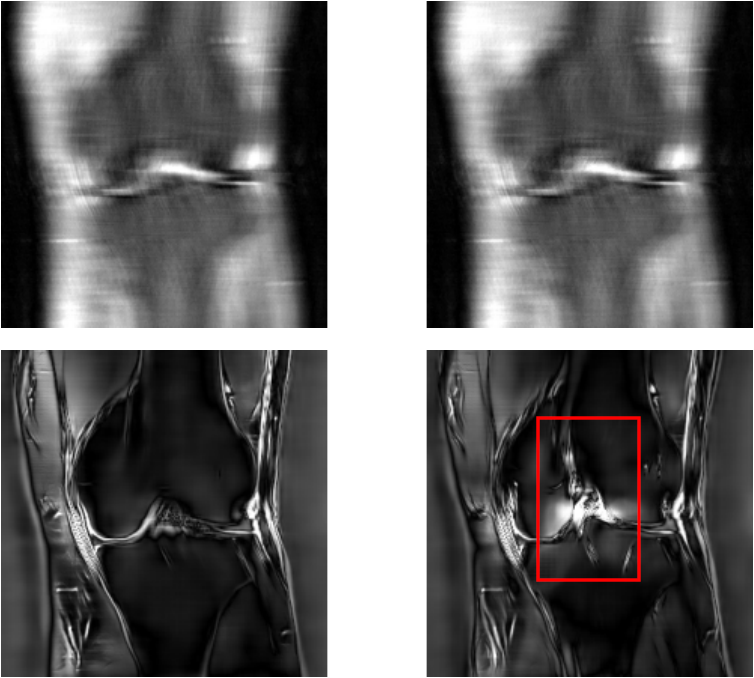

For a qualitative assessment of the results, we show some examples in figure˜0.B.1 for the UNet model and figure˜0.B.2 for the E2E-VarNet model of reconstructions where the attack was successful. These figures are structured as 2x2 panels of images where the first row displays the original and perturbed input samples and the second row displays the corresponding model-based reconstructions. Areas which we believe contain hallucinatory structures are highlighted in red.

We notice from LABEL:fig:unet-best1 and LABEL:fig:unet-best2 that the multi-coil images seem to be more vulnerable than the single-coil ones, in the sense that the resulting distortions are more severe for multi-coil data. The generated perturbations also seem easier to spot for single-coil data. This may be explained by the fact that perturbations in the multi-coil images can be more “spread out” across the coils, whereas with single-coil data this is not possible. This is consistent with the observation that vulnerability to adversarial examples increases with data dimensionality [14, 27]. Although we cannot compare to single-coil data for the E2E-VarNet, we do notice large distortions in LABEL:fig:varnet-best1 as well that go far beyond the boundaries of our inserted detail. On the multi-coil brain data, the hallucinations seem less severe for both models compared to the knee data, but the distortions can still be significant as they tend to resemble non-existent sulci. For knee images, the distortions appear to substantially change the structure of the knee joint, especially on multi-coil data.

We conclude that the adversarially perturbed samples can lead to realistic reconstructions which exhibit biologically plausible distortions that could mislead expert interpretation, and that the insertion of the artificial detail will often cause further distortion beyond the original target region. For both models, this is especially apparent in the multicoil knee data, where the shape of the knee joint tends to change significantly when the detail is inserted.